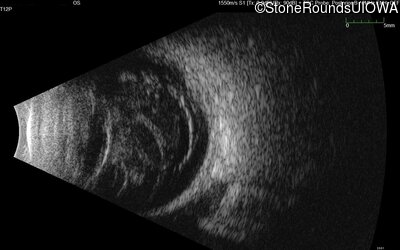

B-Scan Ultrasonography - Right - 20/300 sc

Exemplar